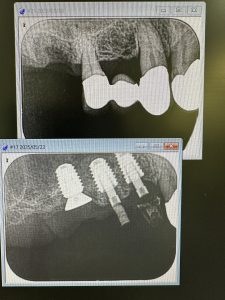

私は、朝からインプラント3本スキャナー印象

昼間からは、危ない動脈近接のソケットリフト

バッチリ👍避けるコツがある💪

抜歯後2ヶ月待ちオペ、EMDとボナークのお陰です

違いが、分かるかなあ?